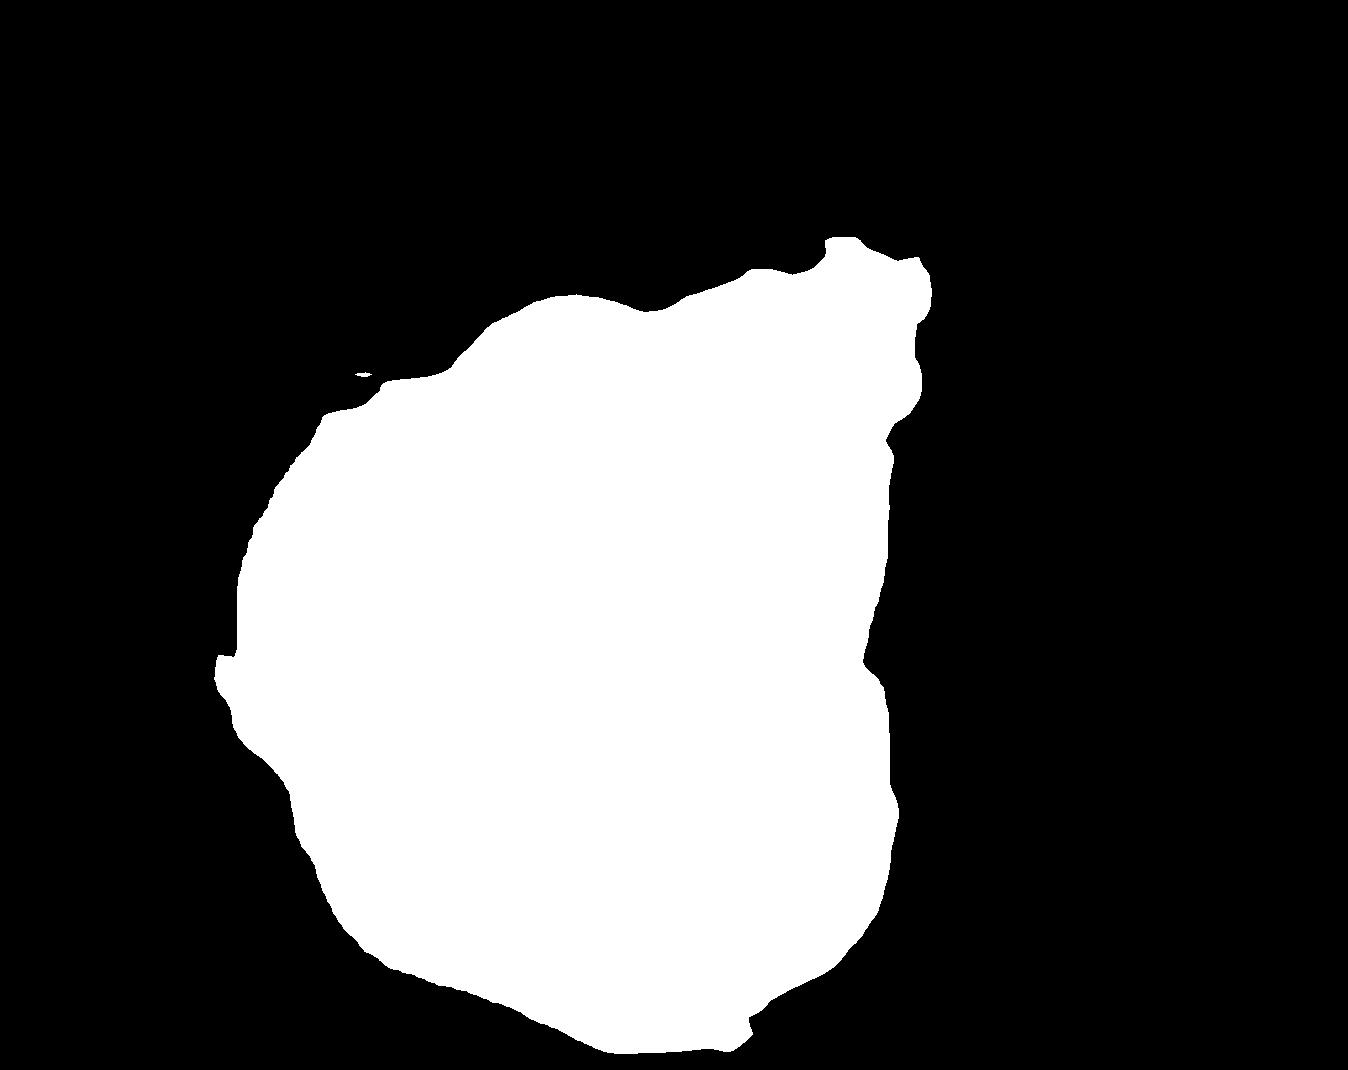

Figure 4 shows some example masks predicted by our best performing model (DivergentNets) together with masks produced by the intermediate models. We see that each intermediate model learns slightly different features, making an overall more precise segmentation mask when combined. For example, the first row of Figure 4 shows the predicted masks and ground truth of a large polyp. We see that each model predicts slightly different masks for the same input and that TriUNet over-estimates the size of the polyp. After averaging the predicted masks for DivergentNets’ final output, this area is smoothed out by the predictions from the other intermediate models.

Even though DivergentNets primarily produces more accurate masks than any single model, there are cases where masks from the intermediate model better match the ground truth. We see this in row three, where DeepLabv3+ produces a more precise mask than all other intermediate models, making the averaged output less accurate.